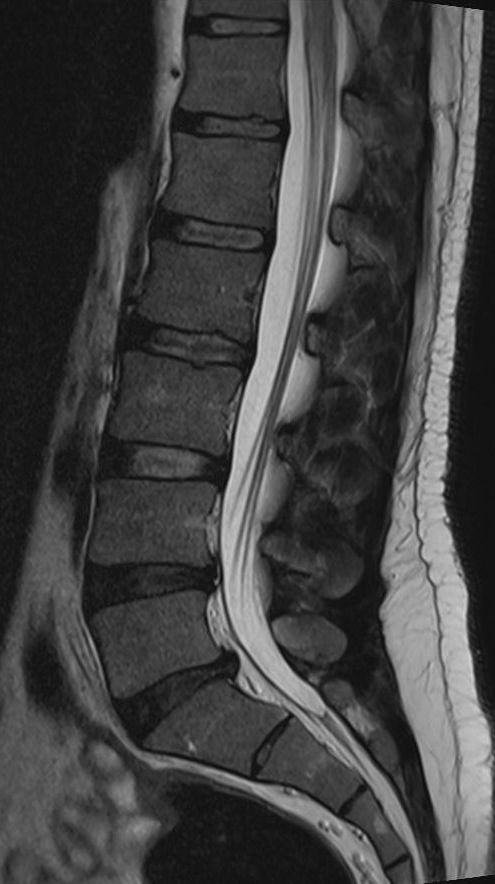

MRT der Wirbelsäule und ISG

MRT Wirbelsäule

Eine MRT der Wirbelsäule (MRT HWS, MRT BWS oder MRT LWS) stellt Bandscheibe und Wirbelkörper gut dar und wird u.a. durchgeführt bei Rückenschmerzen, Verdacht auf Bandscheibenvorfall oder Spinalkanalstenose. Sie kann sehr gut zwischen

alter und frischer Wirbelkörperfraktur differenzieren.